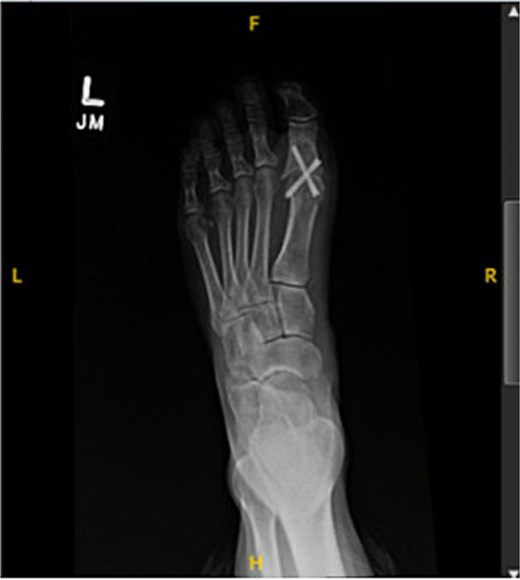

A 44-year-old active woman, with a body mass index of 19.7, presented with symptomatic left hallux rigidus. Her past medical history included only celiac disease; she had no history of smoking, diabetes, peripheral vascular disease, or other conventional vascular risk factors. Her sole medication was spironolactone. She underwent standard first MTP arthrodesis with articular surface preparation, demineralized bone matrix, and fixation using two headless compression screws (Fig. 1). A tourniquet was applied just above the ankle; however, the exact duration was not available because the procedure was performed at an outside hospital. She received perioperative cefazolin prophylaxis.

Postoperative radiograph showing first metatarsophalangeal joint arthrodesis with two headless compression screws.